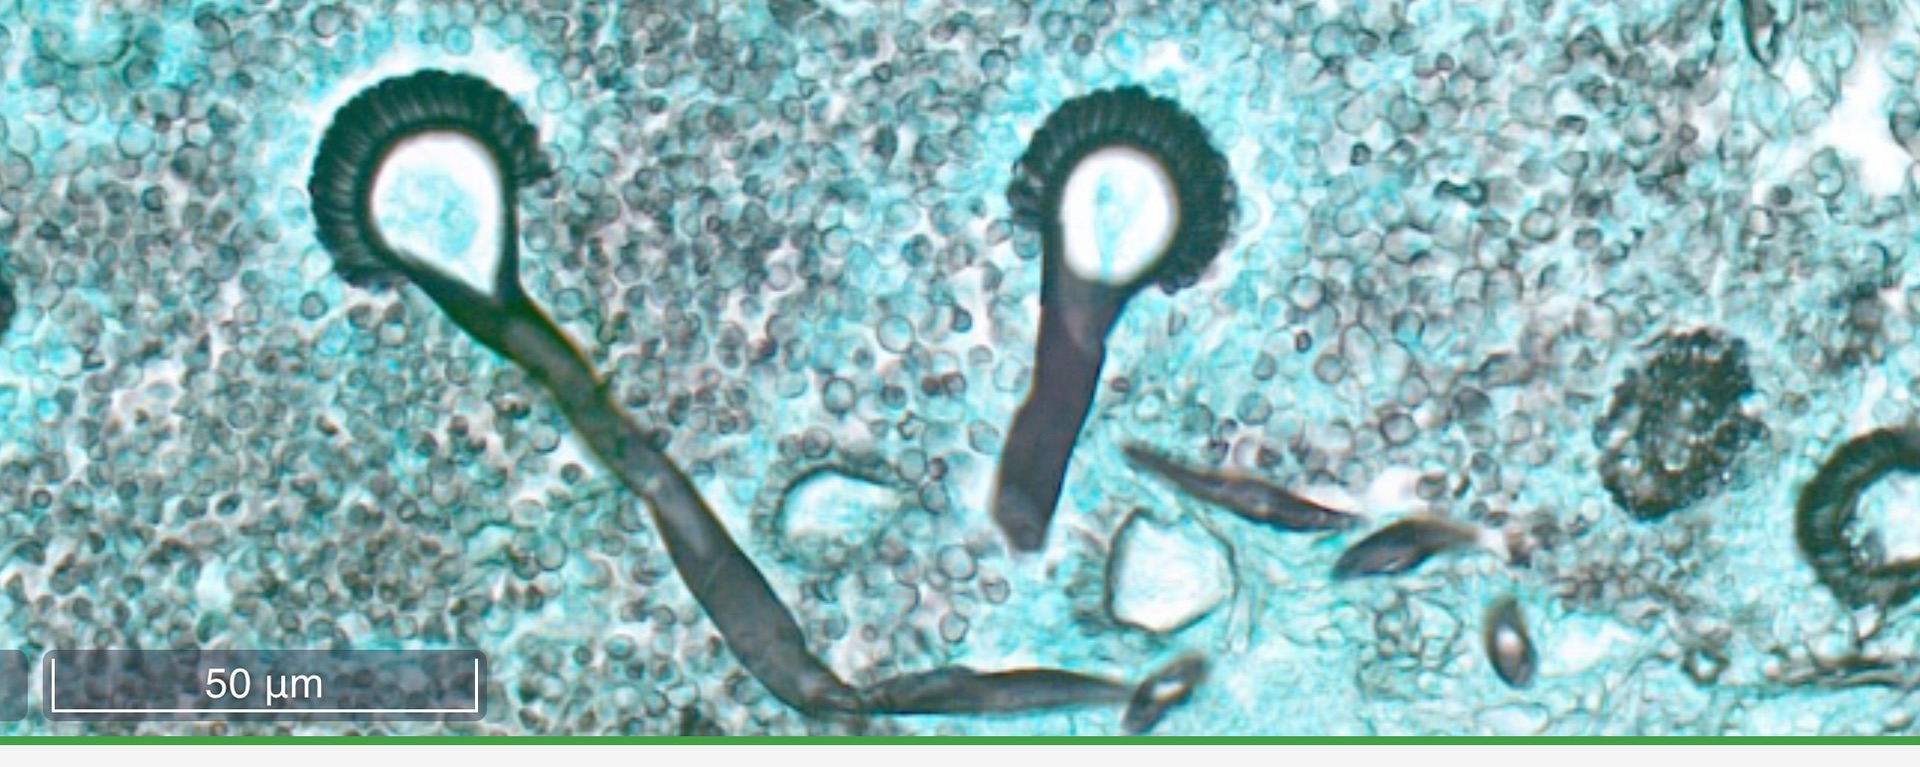

Aspergillose Lunge

Grocott Färbung

Hier besonders, Ausbildung von Konidien, welche sich im Schnitt als kleine Perückenköpfe zeigen.